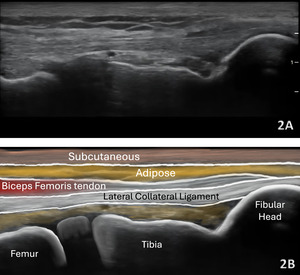

Normal Sonographic Appearance

In the LAX view, depending on the probe width and size, one should start distally to visualize the hyperechoic reflection of the bony cortex of the fibular head distally and the cortex of the femoral epicondyle more proximally. If the depth is increased enough, you will also be able to visualize the bony reflection of the tibia directly below the fibular head. Usually, the LCL demonstrates a hyperechoic fibrillar pattern. The distal portion of the tendon may appear heterogeneous and thickened due to the bifurcating distal biceps femoris tendon that runs both superficial and deep to the LCL.9